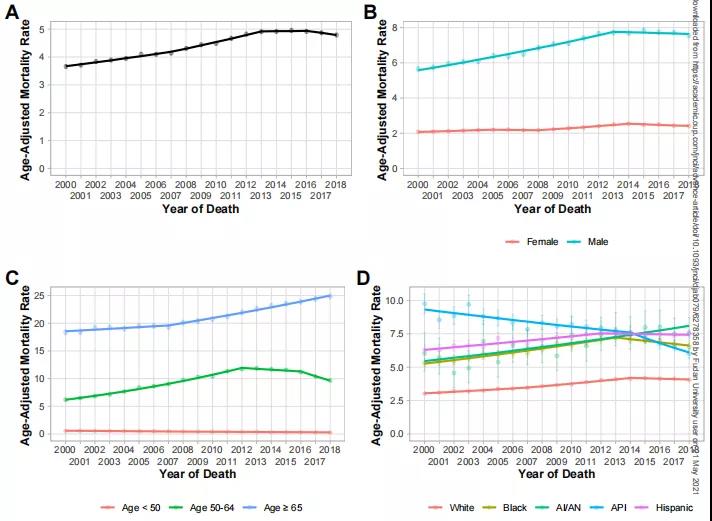

在中位时间长达7.9年的随访期间,有1612例肝细胞癌新发病例和5017例与肝病有关的死亡。尽管阿司匹林服用者普遍年纪更大,基础心血管状况更差,但肝细胞癌发病风险和肝病相关死亡风险都更低!

阿司匹林服用者的肝细胞癌估算累积发病率为4.0%,而非阿司匹林服用者中这一数字为8.3%。调整其他混杂影响因素后,服用阿司匹林的慢性病毒性肝炎人群,发生肝细胞癌的风险大幅降低了31%。

进一步分析发现,随着持续服用阿司匹林的时间延长,风险降低程度会越发明显。相比较于短期服用阿司匹林3个月-不足1年的慢性病毒性肝炎人群:

服用1年-不足3年,肝细胞癌风险进一步降低10%,78p帝国网站管理系统

服用3年-不足5年,肝细胞癌风险进一步降低34%,78p帝国网站管理系统

服用5年及以上,肝细胞癌风险进一步降低43%。78p帝国网站管理系统

在服用者和非服用者中,10年肝病相关死亡率分别为11%和17.9%。调整其他混杂影响因素后,服用阿司匹林的慢性病毒性肝炎人群,死于肝脏问题的风险大幅降低27%。

在10年胃肠道出血风险方面,服用阿司匹林的影响不大。服用组和非服用组的发生率为7.8%和6.9%,没有显著差异。

研究团队承认回顾性研究有所局限,比如受试人群仅限于病毒性肝炎白人患者,也缺乏一些潜在相关信息,如吸烟、丙肝病毒根除或乙肝病毒DNA水平、肝纤维化分期、肝细胞癌筛查、黄曲霉素暴露等。因此,他们提出,“我们的发现支持,有必要进行随机临床试验来检验阿司匹林用于肝细胞癌一级预防的益处。从而进一步阐明启动阿司匹林治疗的适当时机、最短必要的治疗持续时间,以及在其他人群中的效果。”

在全球范围内,每年新发肝细胞癌超过50万例,而且主要与慢性感染乙肝或丙肝病毒有关。尽管现有药物可以抑制乙肝病毒,丙肝已经能够被治愈,但乙肝和丙肝患者仍然有相对较高的风险发展为肝硬化,甚至肝癌。对这些慢性肝炎病毒感染者来说,有效预防病情发展的策略将大大改善他们的预后。